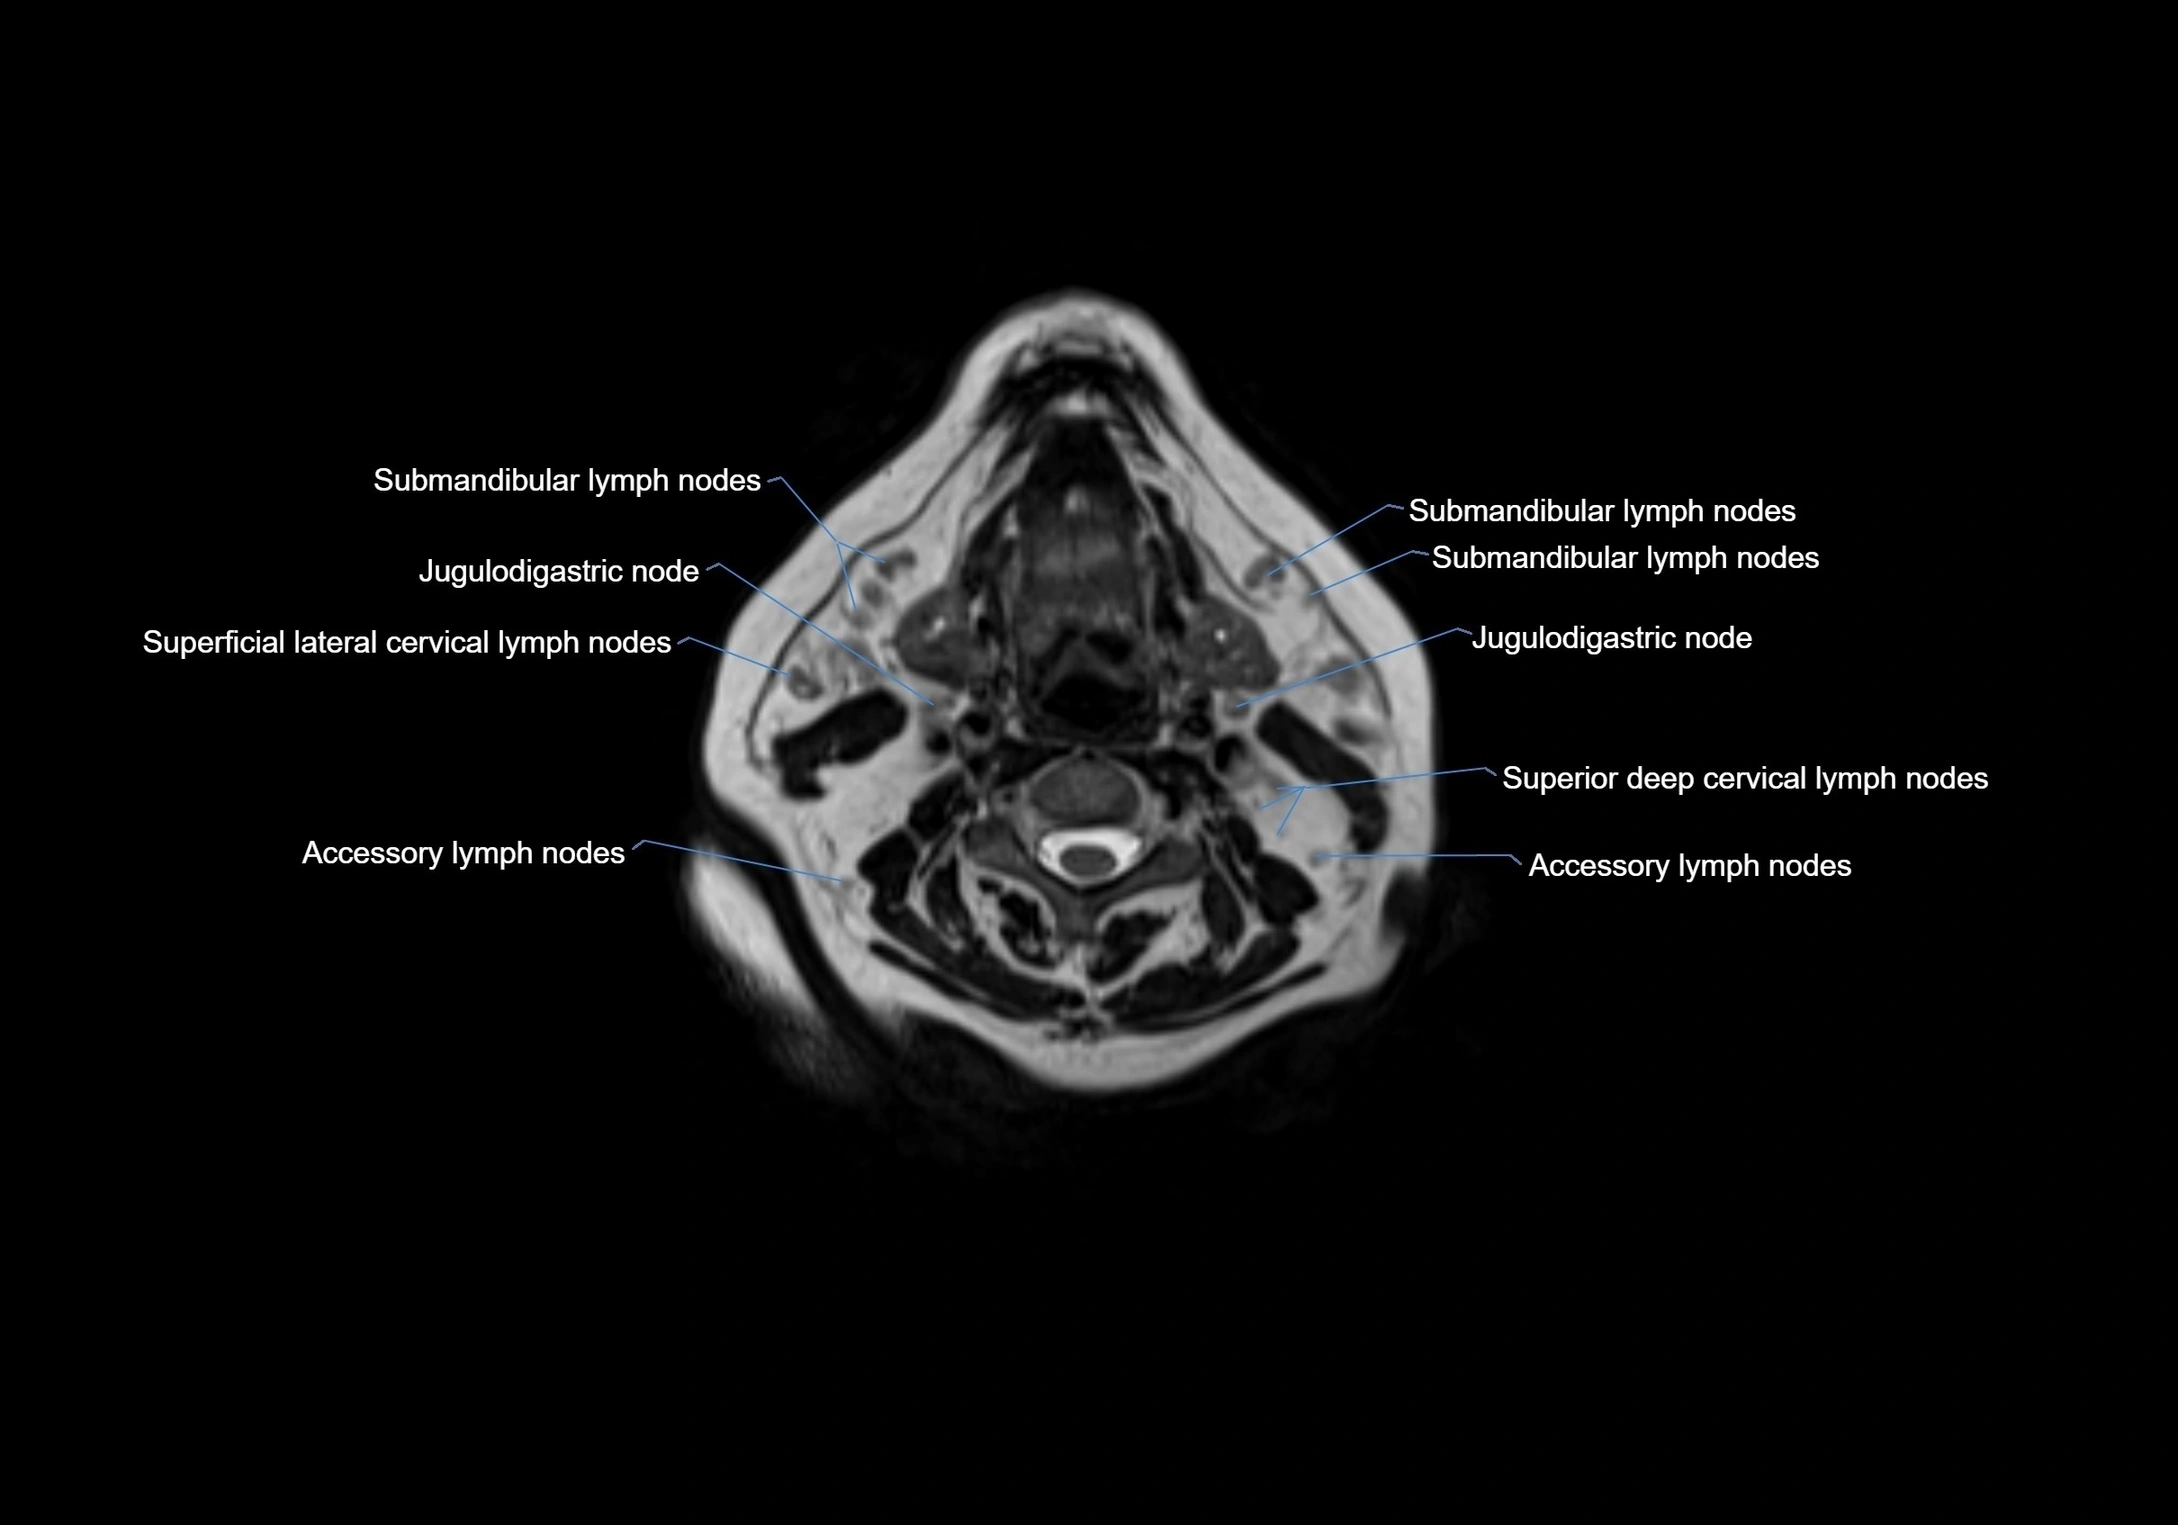

MRI Appearance

T1-weighted images:

• Normal accessory nodes appear as small, oval hypointense to intermediate signal structures within subcutaneous fat

• Surrounded by hyperintense fat, enhancing contrast for visualization

• Pathological nodes may appear enlarged or rounded, sometimes with cortical thickening

T2-weighted images:

• Nodes show intermediate signal, with surrounding fat bright

• Useful for detecting edema, inflammation, or infiltration

• Fatty hilum may appear slightly hyperintense relative to cortex

MRI images

image